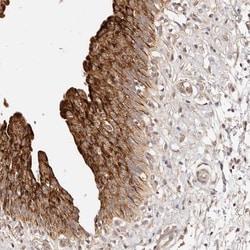

Invitrogen™ CCL14 Polyclonal Antibody

Brand: Invitrogen™ PA556421

| Immunohistochemistry (Paraffin) | |